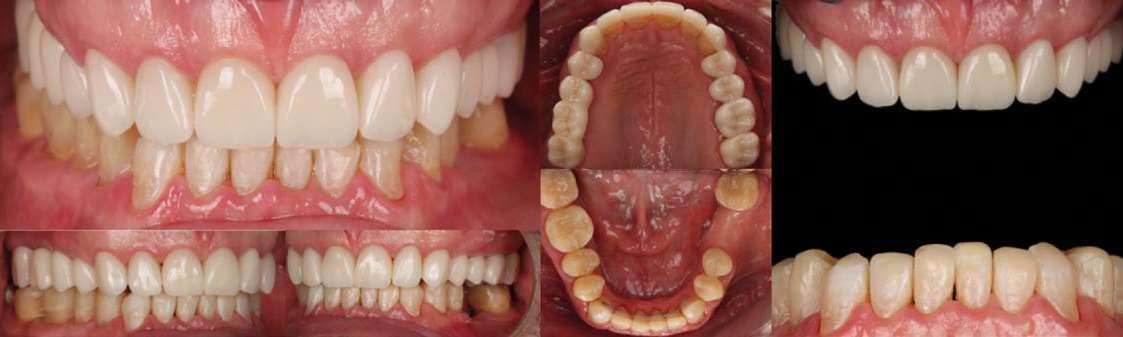

Presentación del caso

Paciente varón de 51 años que acudió a la Clínica Universitaria Odontológica (CUO) de la Universitat Internacional de Catalunya motivado por la necesidad de mejorar tanto su salud bucal como la estética de su sonrisa. El paciente manifestaba sensibilidad dental frecuente, especialmente al frío, episodios de incomodidad funcional durante la masticación y una marcada disconformidad con la apariencia estética de sus dientes. Entre sus principales expectativas destacó el deseo de obtener una rehabilitación integral que le proporcionara confort funcional y un resultado estético natural, siempre evitando procedimientos quirúrgicos o tratamientos excesivamente invasivos.

En la exploración clínica inicial se observaron signos compatibles con desgaste dental generalizado, pérdida de estructura dentaria a nivel incisal y oclusal, y presencia de restauraciones previas con

distintos grados de desajuste marginal. Se evidenció también una leve recesión gingival localizada y alteraciones en la alineación dentaria que afectaban a la estética de la sonrisa. El estado periodontal general era aceptable, con índices de placa y sangrado controlados, sin presencia de movilidad dentaria significativa.

Hallazgos clínicos iniciales

 Desgaste dental generalizado, compatible con erosión en palatinos de sector anterior superior y caras oclusales posteriores.

 Atrición en bordes incisales superiores e inferiores.

 Lesiones cervicales no cariosas (abrasiones por cepillado y abfracciones por sobrecarga oclusal).

 Presencia de puente metal-cerámica 1.5–1.7, con ausencia de piezas 1.6 y 3.6.

 Apiñamiento dental en incisivos inferiores y retroinclinación de incisivos superiores (torque negativo), diagnosticándose Clase II subdivisión 2.

Análisis estético

 Dientes cortos.

 Desgaste incisal irregular.

 Sonrisa alta con exposición gingival excesiva (“gummy smile”).

 Desbalance entre estética rosa y estética blanca.

 Canting anterosuperior.

Se recopilaron registros clínicos como fotografías extraorales e intraorales (Fig. 1–6) y digitales completos, incluyendo escaneados intraorales y registros de movimientos mandibulares. Los datos se integraron en un articulador virtual mediante el software de diseño digital (Exocad), montando los modelos maxilares, archivo de movimientos mandibulares y horquilla en formato STL.

Figura 1-3. Secuencia fotográfica extraoral inicial.

Figura 4-6. Análisis de la sonrisa del paciente.